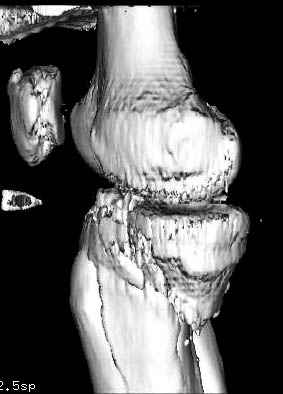

Здесь как раз тот случай, когда результат зависит не только от мастерства хирурга, но и от наличия современных методов исследования. Например, КТ которая поможет рассчитать направления шурупов и установку импланта. Кроме этого, поможет определиться с доступом.

На представленных предоперационных срезах КТ огромный задне-медиальный фрагмент расположен больше кзади, чем медиально. Для планирования, кроме поперечных срезов, надо ориентироваться на корональные срезы, которые укажут топографию верхушки медиального фрагмента.